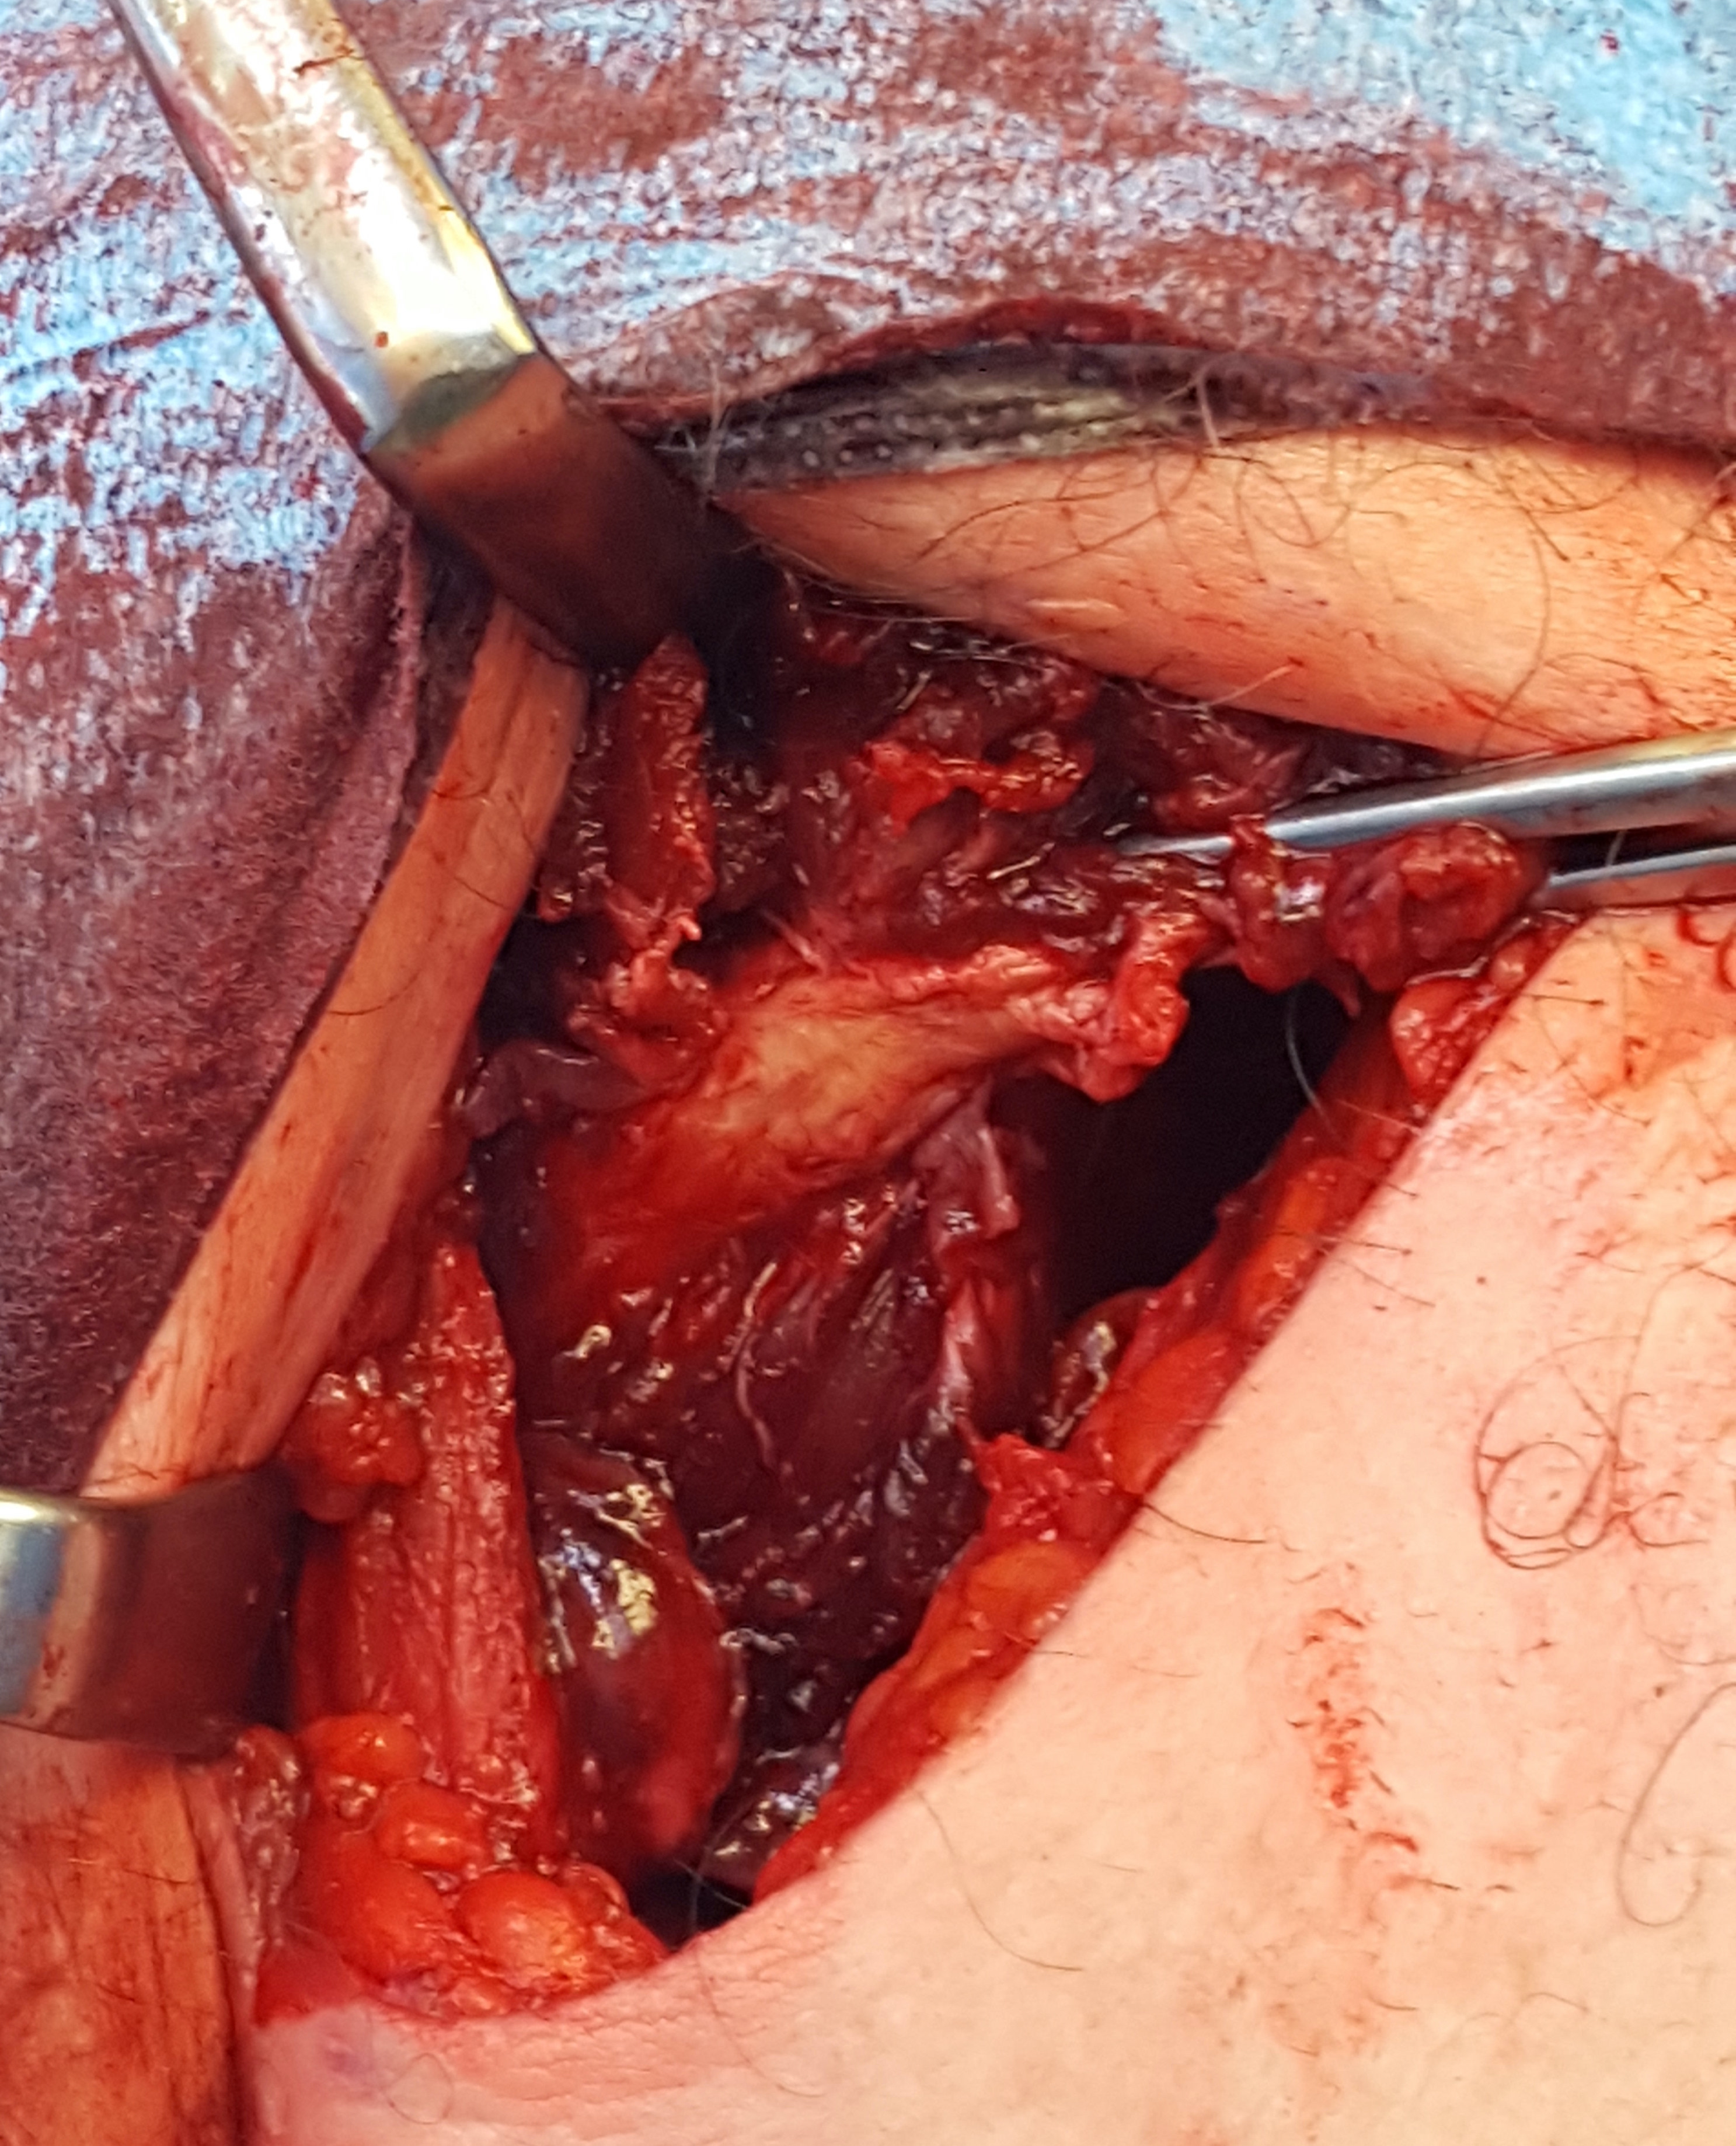

Pec major repair 1

Axillary crease incision in right shoulder, with Kocher forceps on the torn pectoralis major tendon